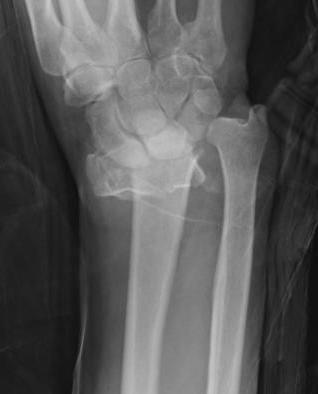

Unacceptable reduction

1. Distal radial Step > 2mm

- leads to RC OA radiographically

- not proven to lead to dysfunction

2. Articular incongruency sigmoid notch / DRUJ > 2 mm

3. Radial shortening > 5 mm

- leads to ulnocarpal abutment

4. Radial inclination < 15o

5. Sagittal tilt

- > 15o dorsal

- > 20o volar

- +/- marked dorsal comminution

7. Risk carpal subluxation

- Barton's fracture / dorsal Barton's